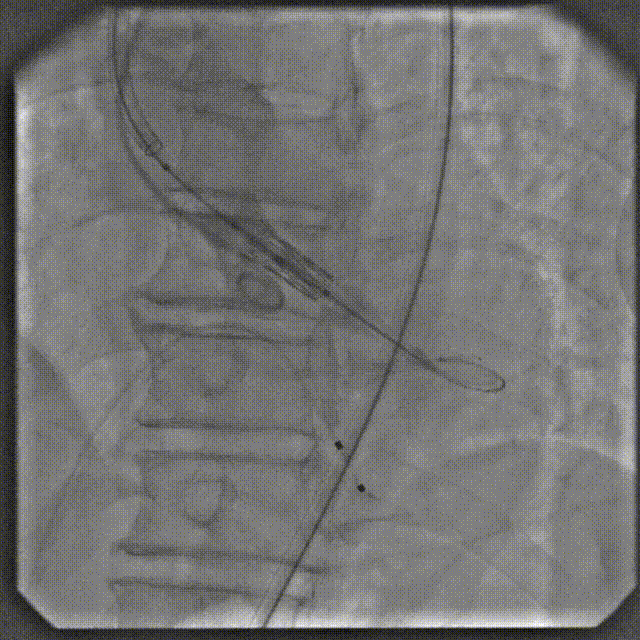

手术过程

根部造影

跨瓣

球扩

定位

释放后造影

后扩

最终造影

术后复查造影示瓣膜位置满意,形态良好,冠脉显影良好;TTE示轻中度瓣周漏,少量心包积液;排除入路血管问题,手术圆满成功。